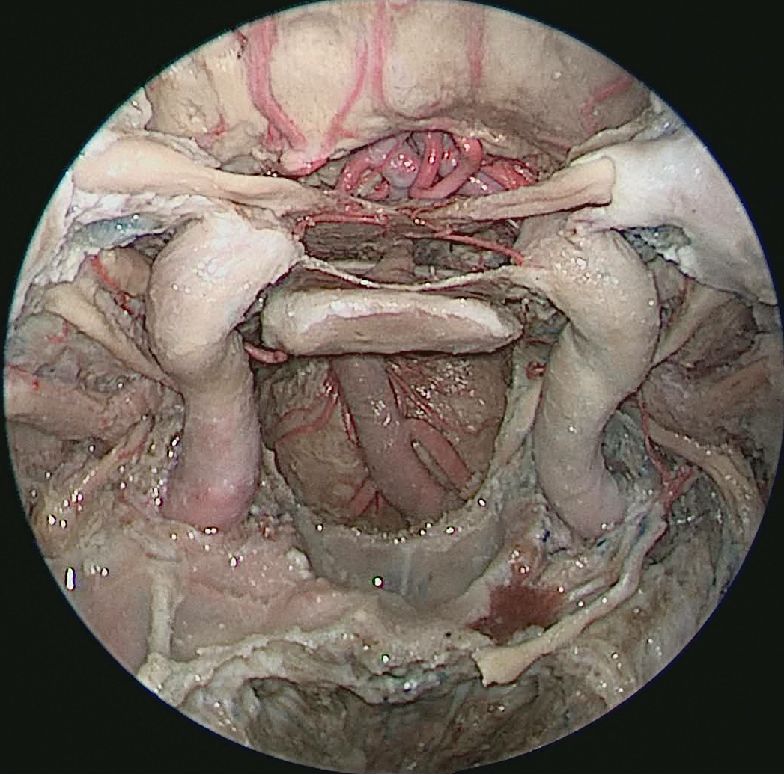

神经内镜在颅底外科的应用-内镜解剖培训班风采

↑ 去除双侧筛窦,观察完整蝶窦前壁